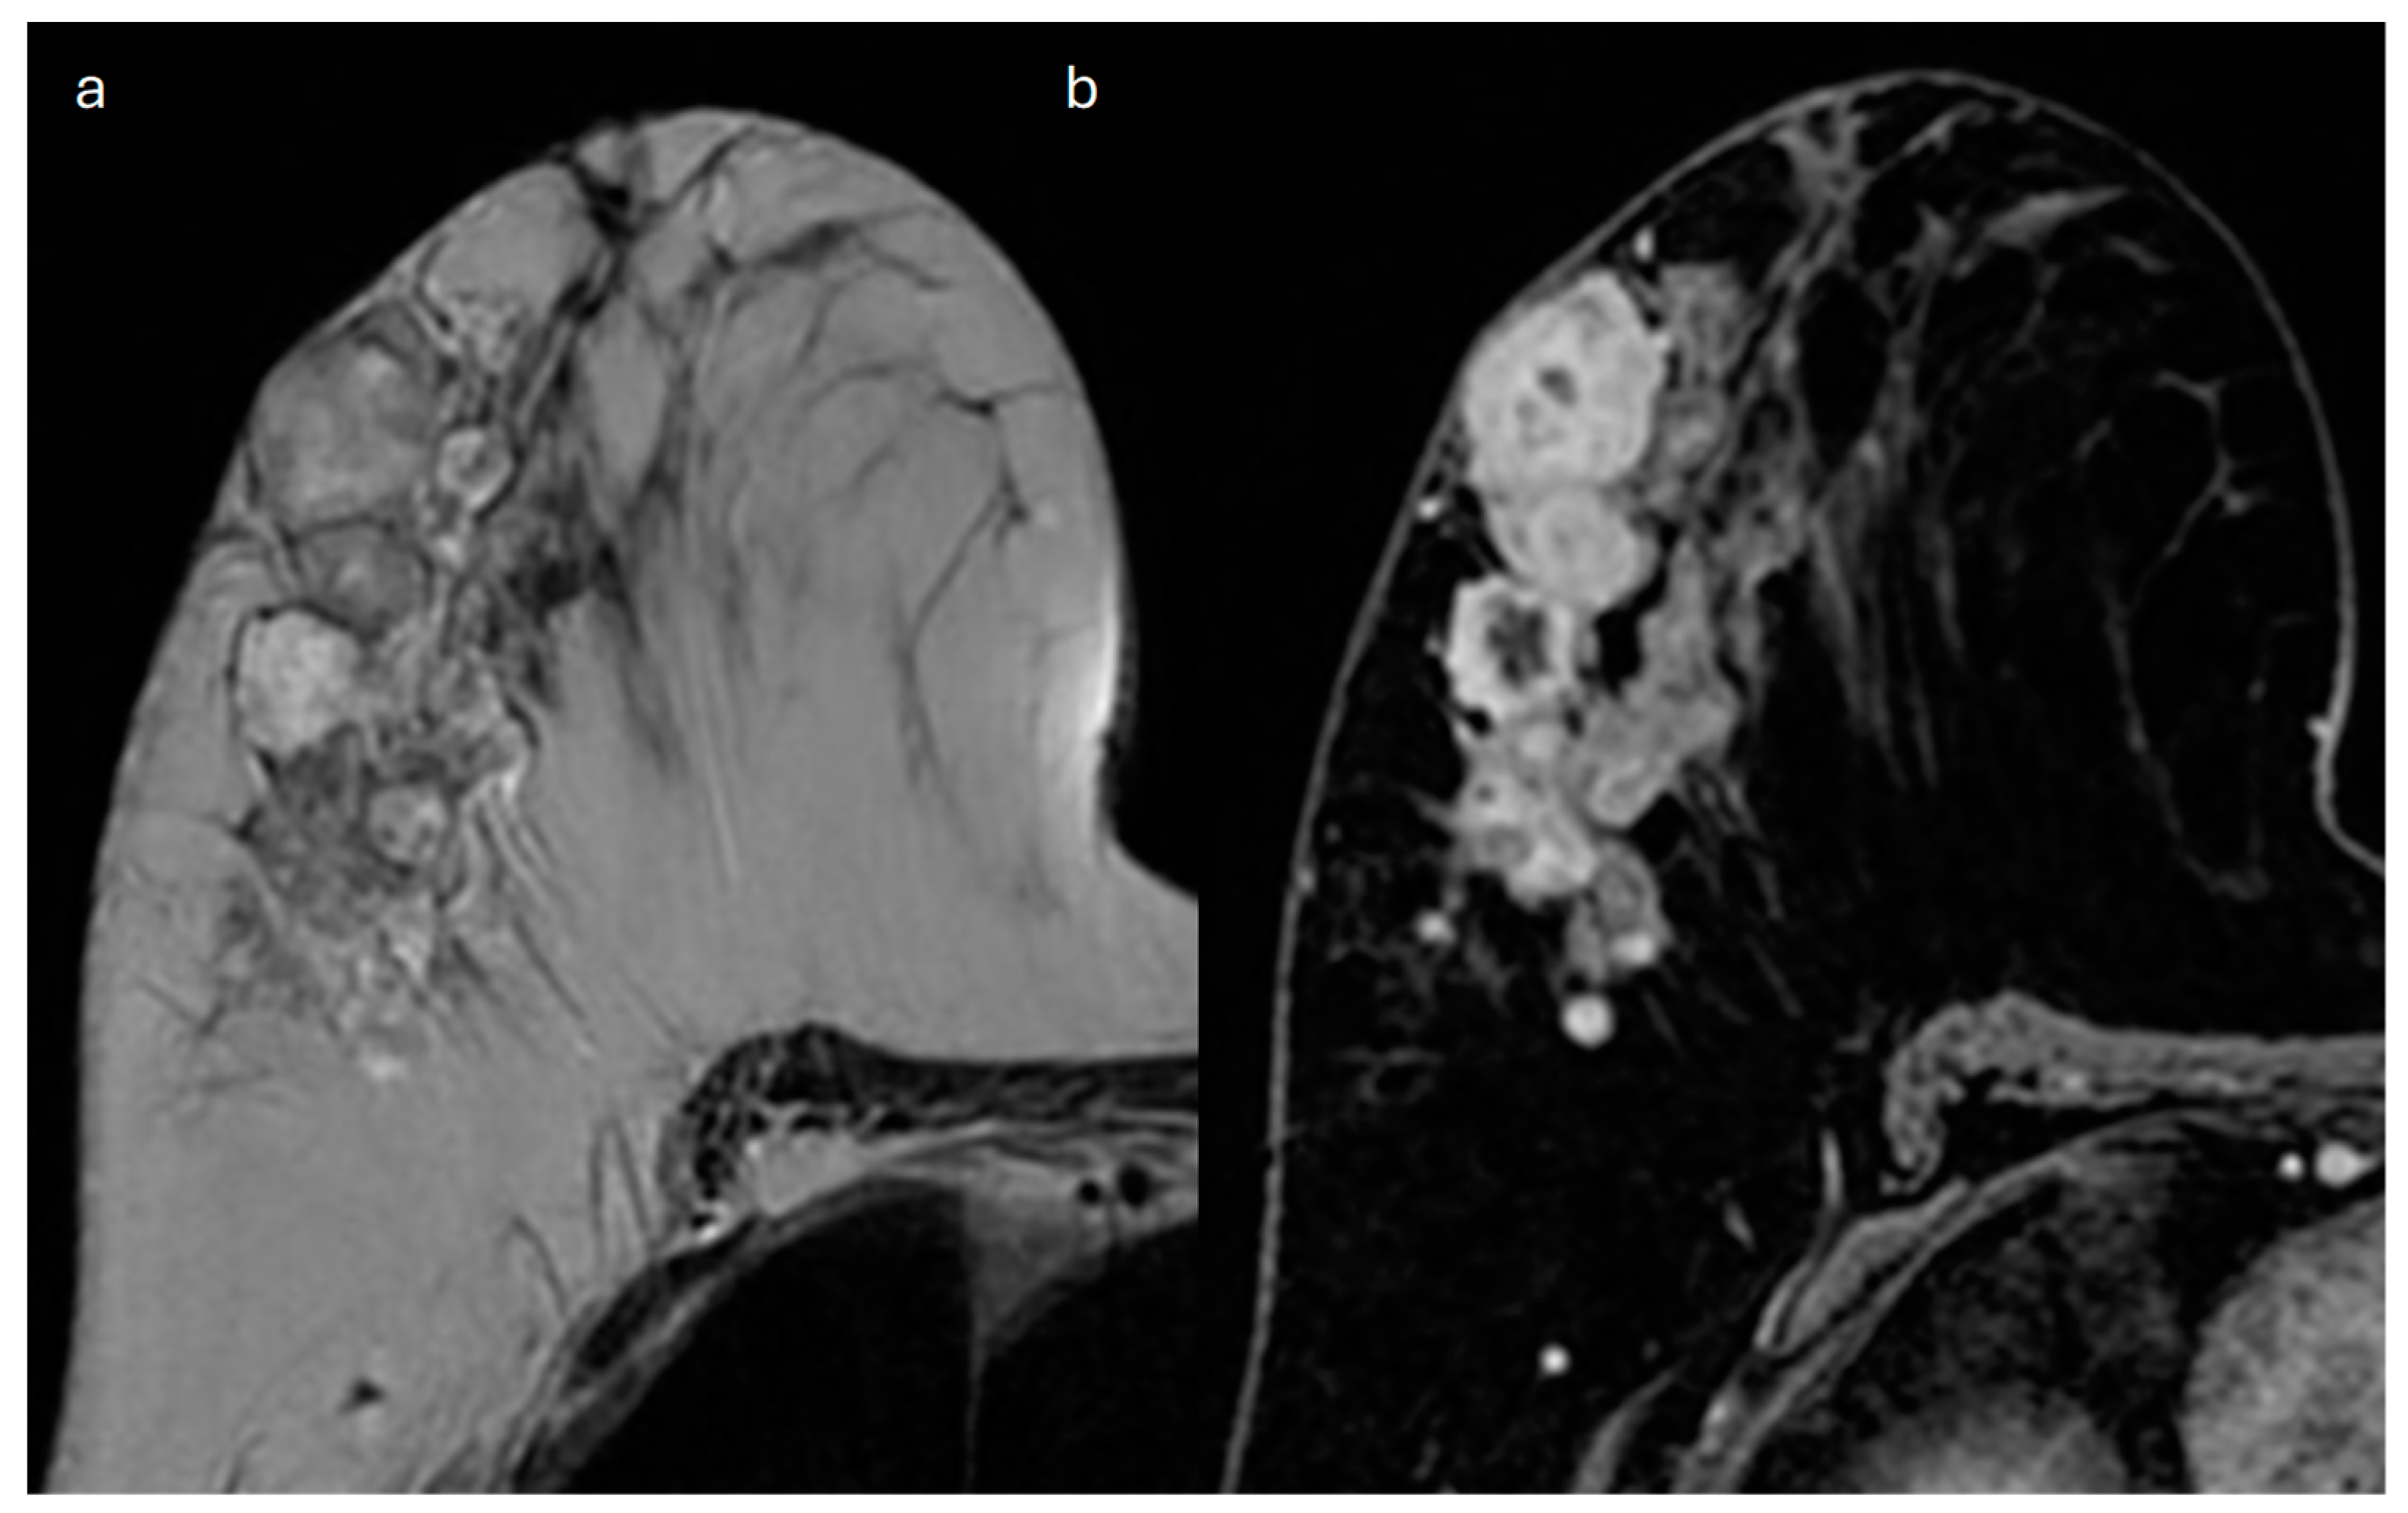

9. Apocrine